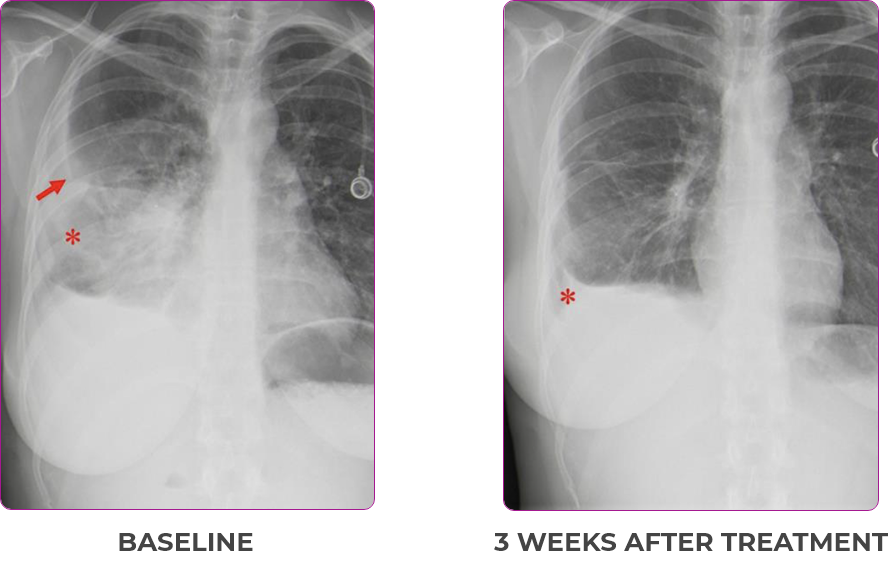

Response in primary and metastatic lesions1

Lung imaging of primary tumors.

SCAN 1: LUNG

SCAN 2: LUNG AND BONE

Images courtesy of Dr Maximilian Hochmair.

Response to VITRAKVI1

- Partial response and symptom improvement confirmed by chest X-rays after <1 month of treatment

- Imaging performed 6 weeks into treatment revealed considerable decrease in the size of both target lesions

- Complete clinical response achieved by 12 months with residual scarring